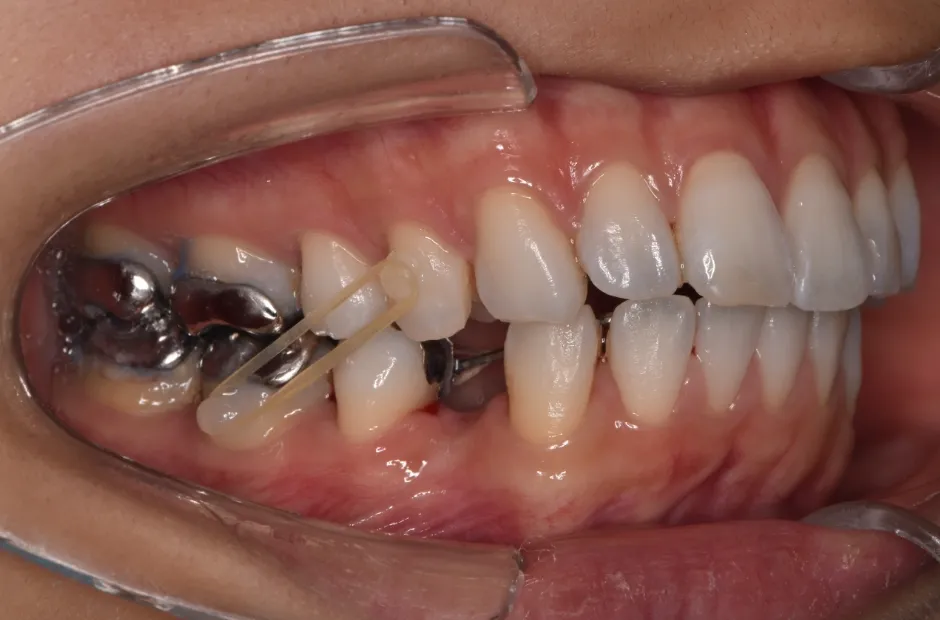

| 診断名・主訴 | 下顎前突、叢生 |

|---|---|

| 年齢・性別 | 23歳・女性 |

| 治療期間・回数 | 3年 |

| 治療に用いた主な装置 | 上顎5,5 下顎4,4 |

| 抜歯部位 | 舌側矯正 |

| 治療費 | 100万円(税抜) |

| リスク・副作用 | 装置による違和感・疼痛・歯肉退縮・歯根吸収・虫歯のリスクなど |

治療前

治療中

治療後